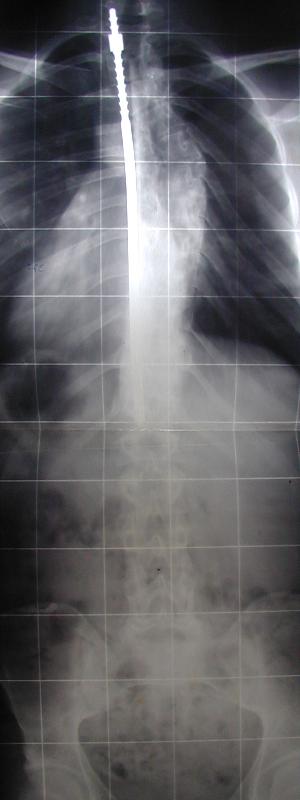

7- opération de la colonne vertébrale : Pour quelle raison a t-on fixé cette tige au niveau de la colonne vertébrale ?

radiographie collège Jules Renard 53000 Laval

Pour la redresser Pour réparer une fracture Pour remplacer les côtes cassées